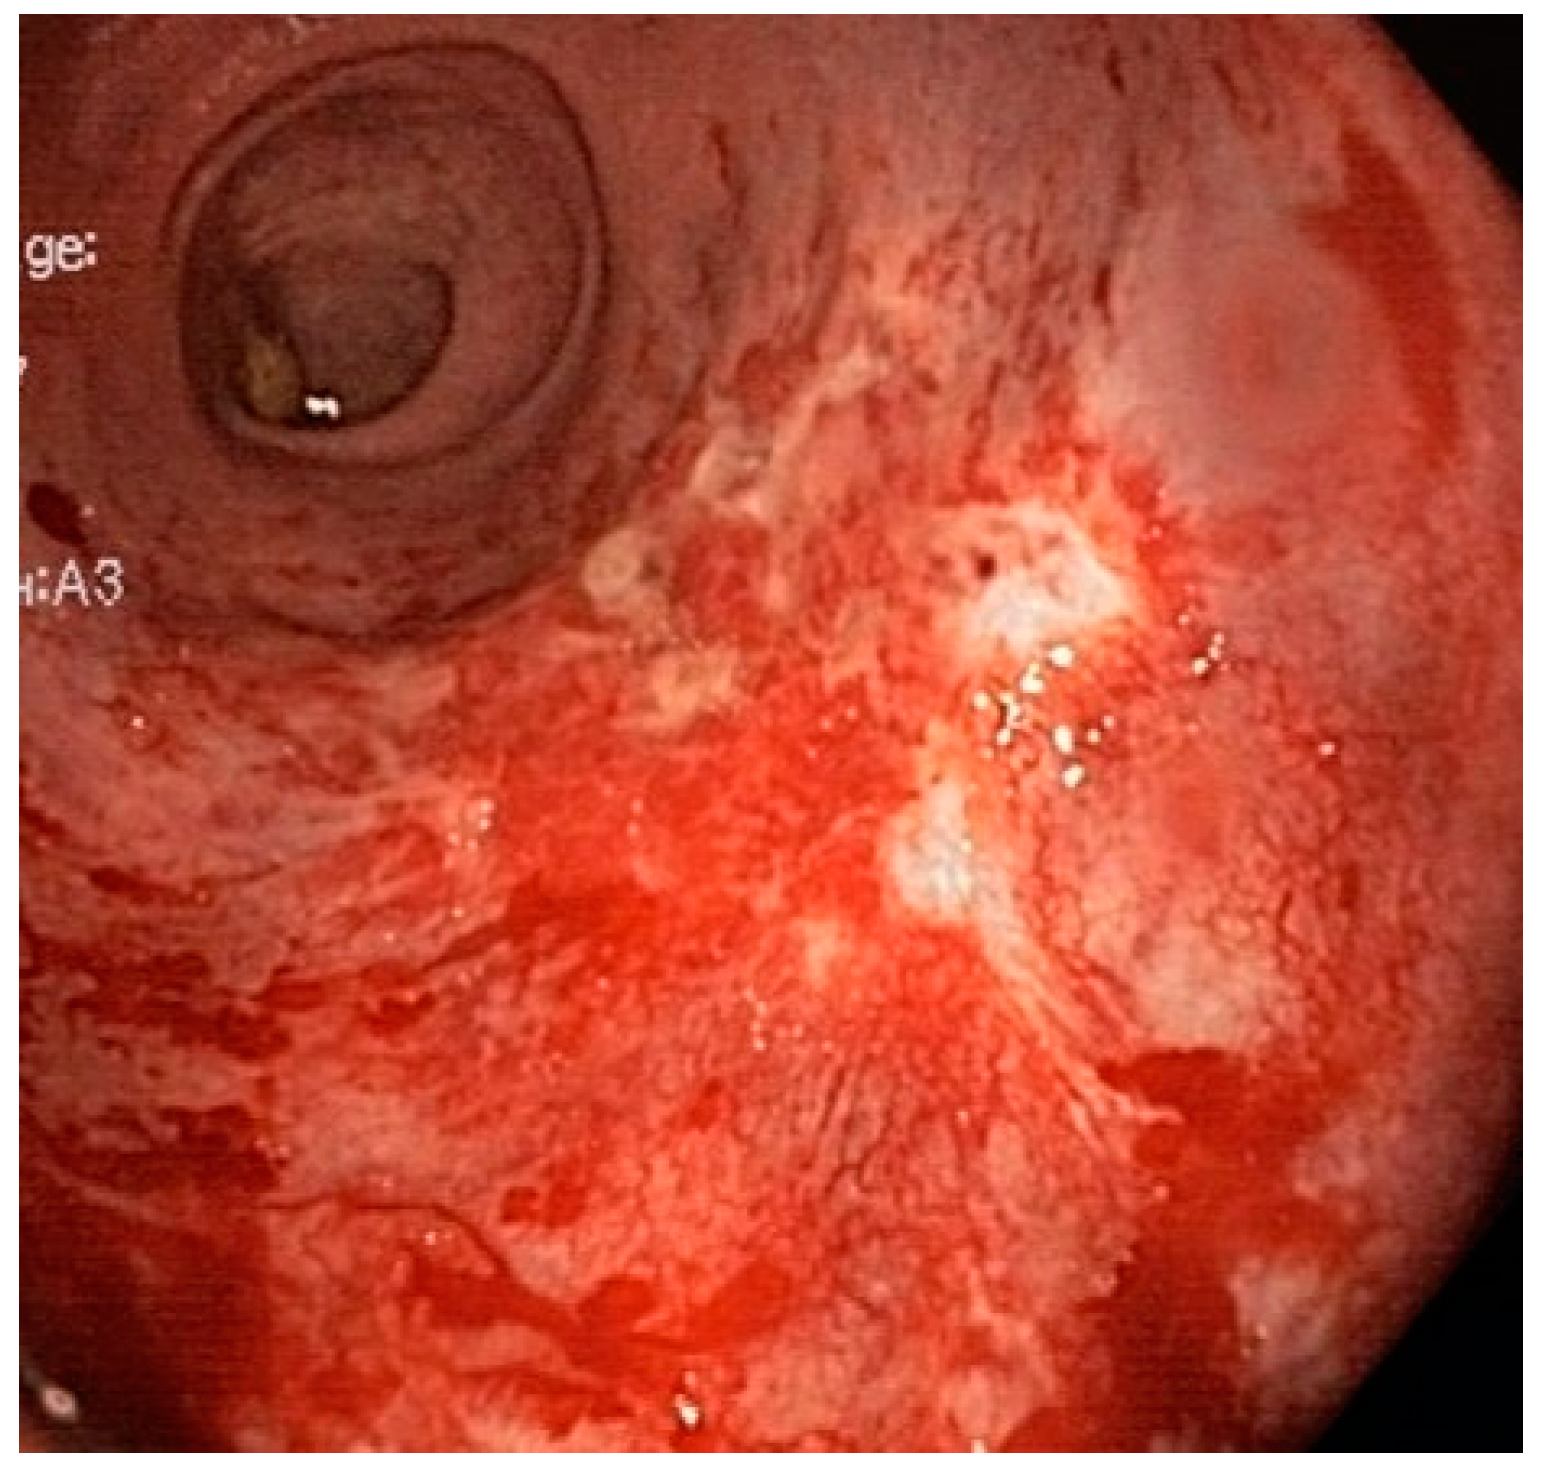

Diode Laser Therapy for Radiation-Induced Vascular Ectasia: Long-Term Results and Cost Analysis

3. Results